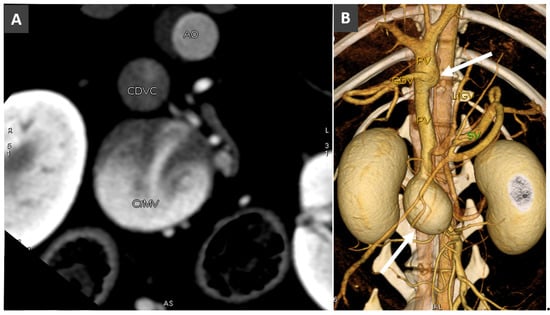

3.2. Portal Vein Hypoplasia

3.7. Acquired Portosystemic Shunts (APSSs)

- Bertolini, G. Acquired portal collateral circulation in the dog and cat. Vet. Radiol. Ultrasound 2010, 51, 25–33. [Google Scholar] [CrossRef]